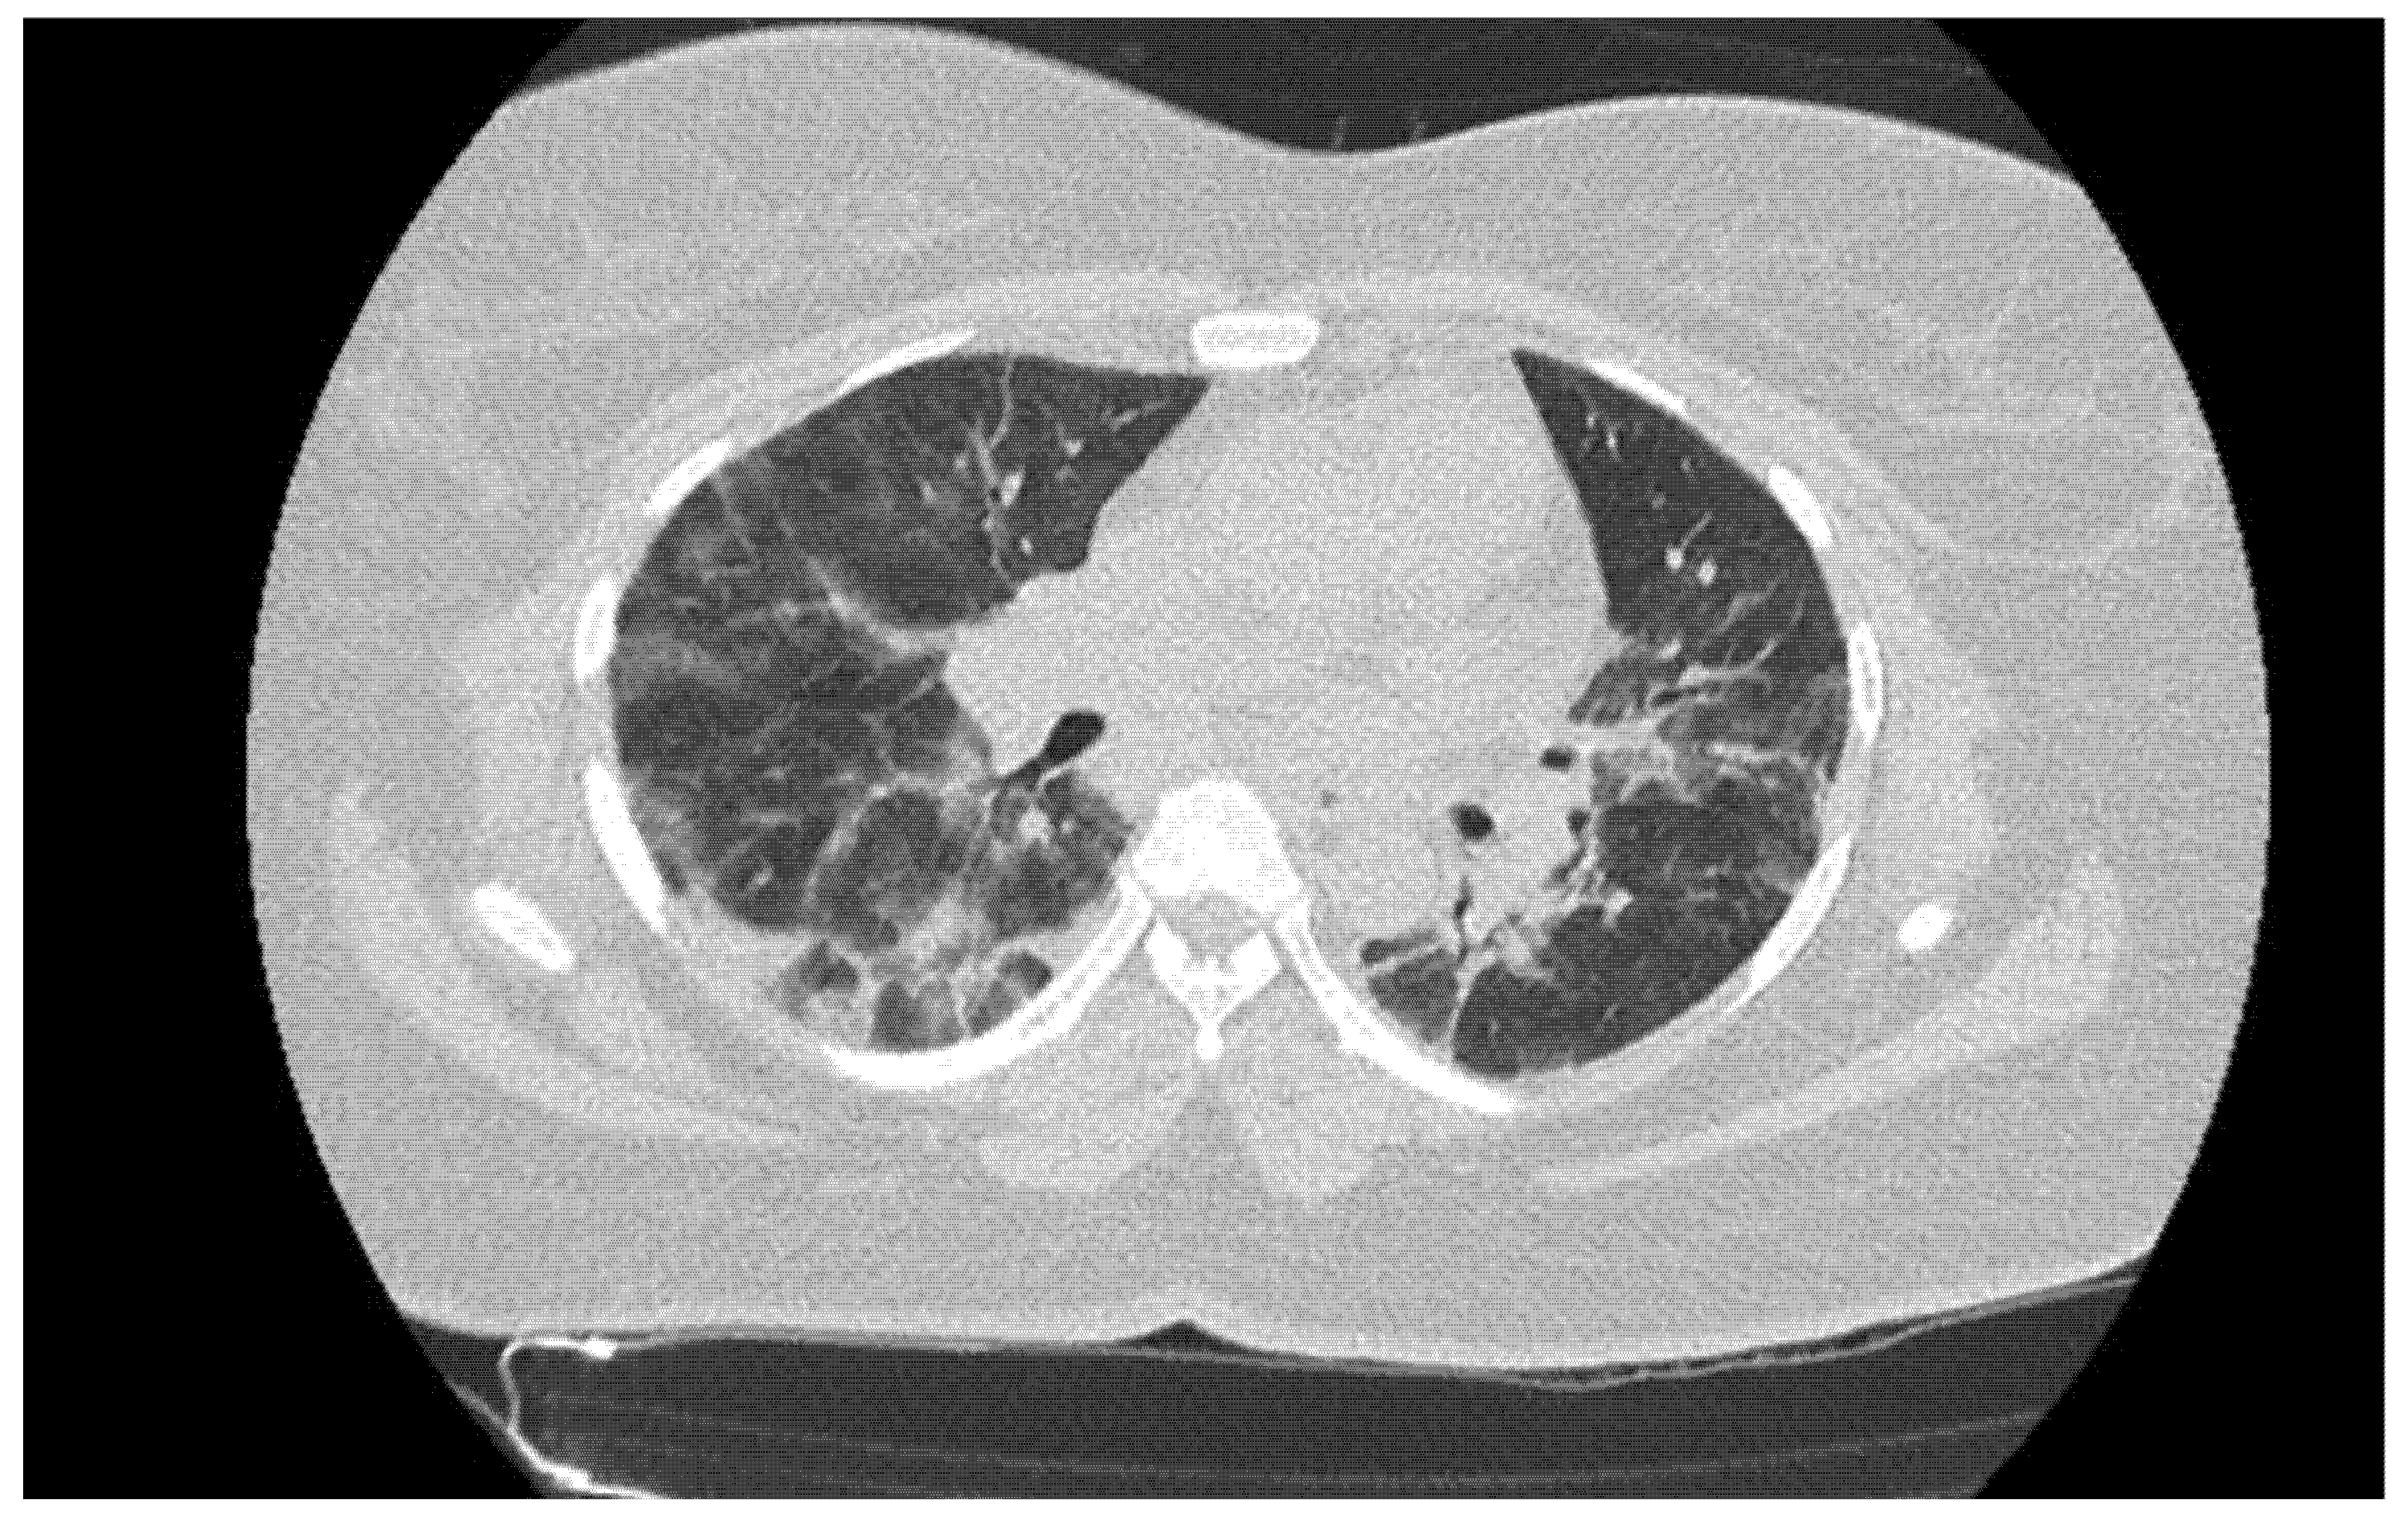

| Chest CT | Compatible | 73 (7.2) |

| Indeterminate | 90 (8.9) | |

| Incompatible | 852 (83.9) | |